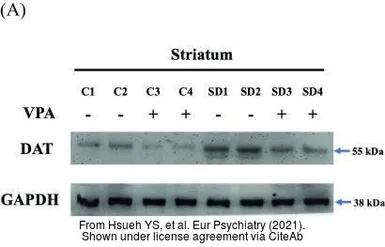

The data was published in the 2021 in Eur Psychiatry. PMID: 33413711